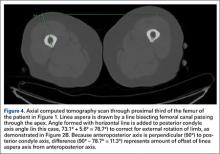

From the most posterior point of the LA, a line drawn forward bisecting the femoral canal defined the LA axis. In type I morphology, the posterior-most point was the apex; in type II, the middle of flat posterior surface was used as the starting point; in type III, the lateral lip was used, as it was sharper than the medial lip. This line is again referenced with a straight horizontal line across the image. The PC angle is then added to account for limb rotation, and the result is the LA angle. As the AP axis is perpendicular to the PC axis, the LA angle is subtracted from 90°; the difference represents the amount of offset of the LA axis from the AP axis. By convention, we assigned this a positive value for an LA lateral to the midpoint of the femur and a negative value for an LA medial to the midpoint (Figure 4).